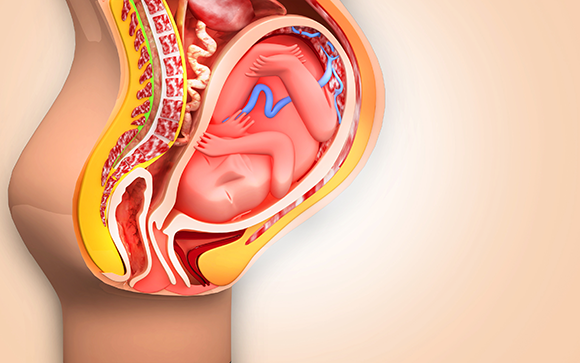

يستوعب الرحم البلاستولا النامية ويوفّر بيئة مناسبة لتطوّر الجنين ونموّه خلال فترة الحمل. جنين في رحم أمّه | الرسم التخطيطيّ: Creations, Shutterstock

ينمو الجنين في تجويف البطن في واحد بالمائة فقط من حالات الحمل المنتبذ (الحمل خارج الرحم)، كما في هذه الحالة. في الصورة: بداية نموّ الجنين في تجويف بطن الأم | الرسم التخطيطيّ: Timonina, Shutterstock